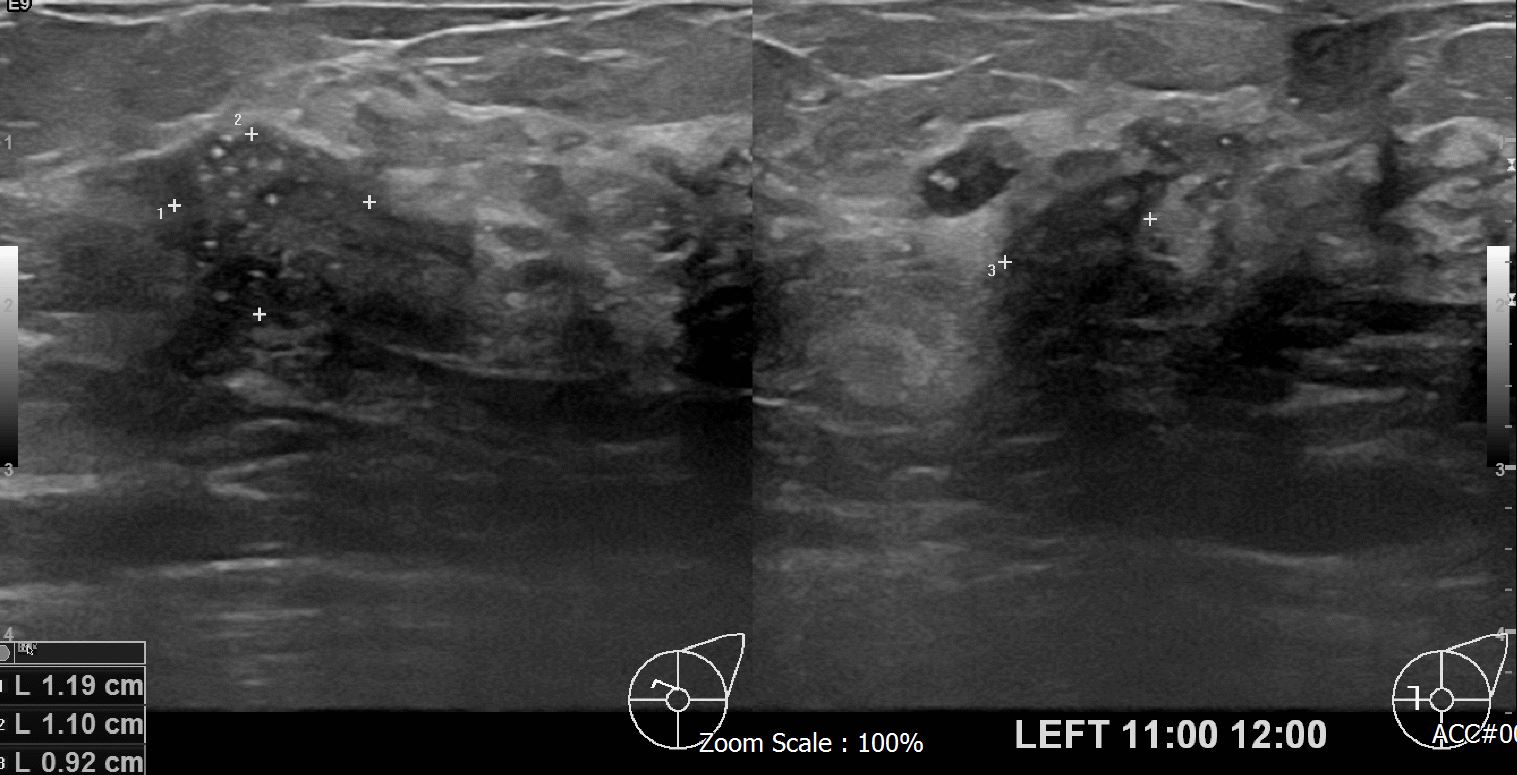

아산유외과 개원후 615번째 유방암 진단

상기환자 외부검사상 이상소견으로 내원하신 70대 여성분으로 좌측유방의 의심스런혹 조직검사 진행해 유방암 진단되었읍니다